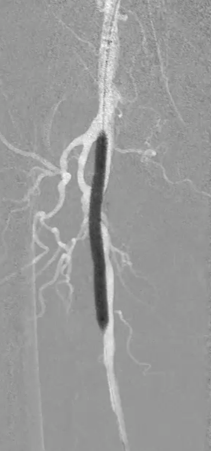

步进造影:股浅动脉起始重度狭窄、中段重度狭窄,腘动脉远端重度狭窄、胫前动脉、胫后动脉闭塞

V-18导丝配合多功能导管通过股浅动脉、腘动狭窄闭塞段,交换0.14导丝远端置于腓动脉中段

步进造影配合血管腔内超声诊断导管提示:股浅动脉全程、腘动脉、胫腓干动脉血流通畅,未见明显夹层、造影剂外溢,远端未见栓塞,膝下动脉如前。